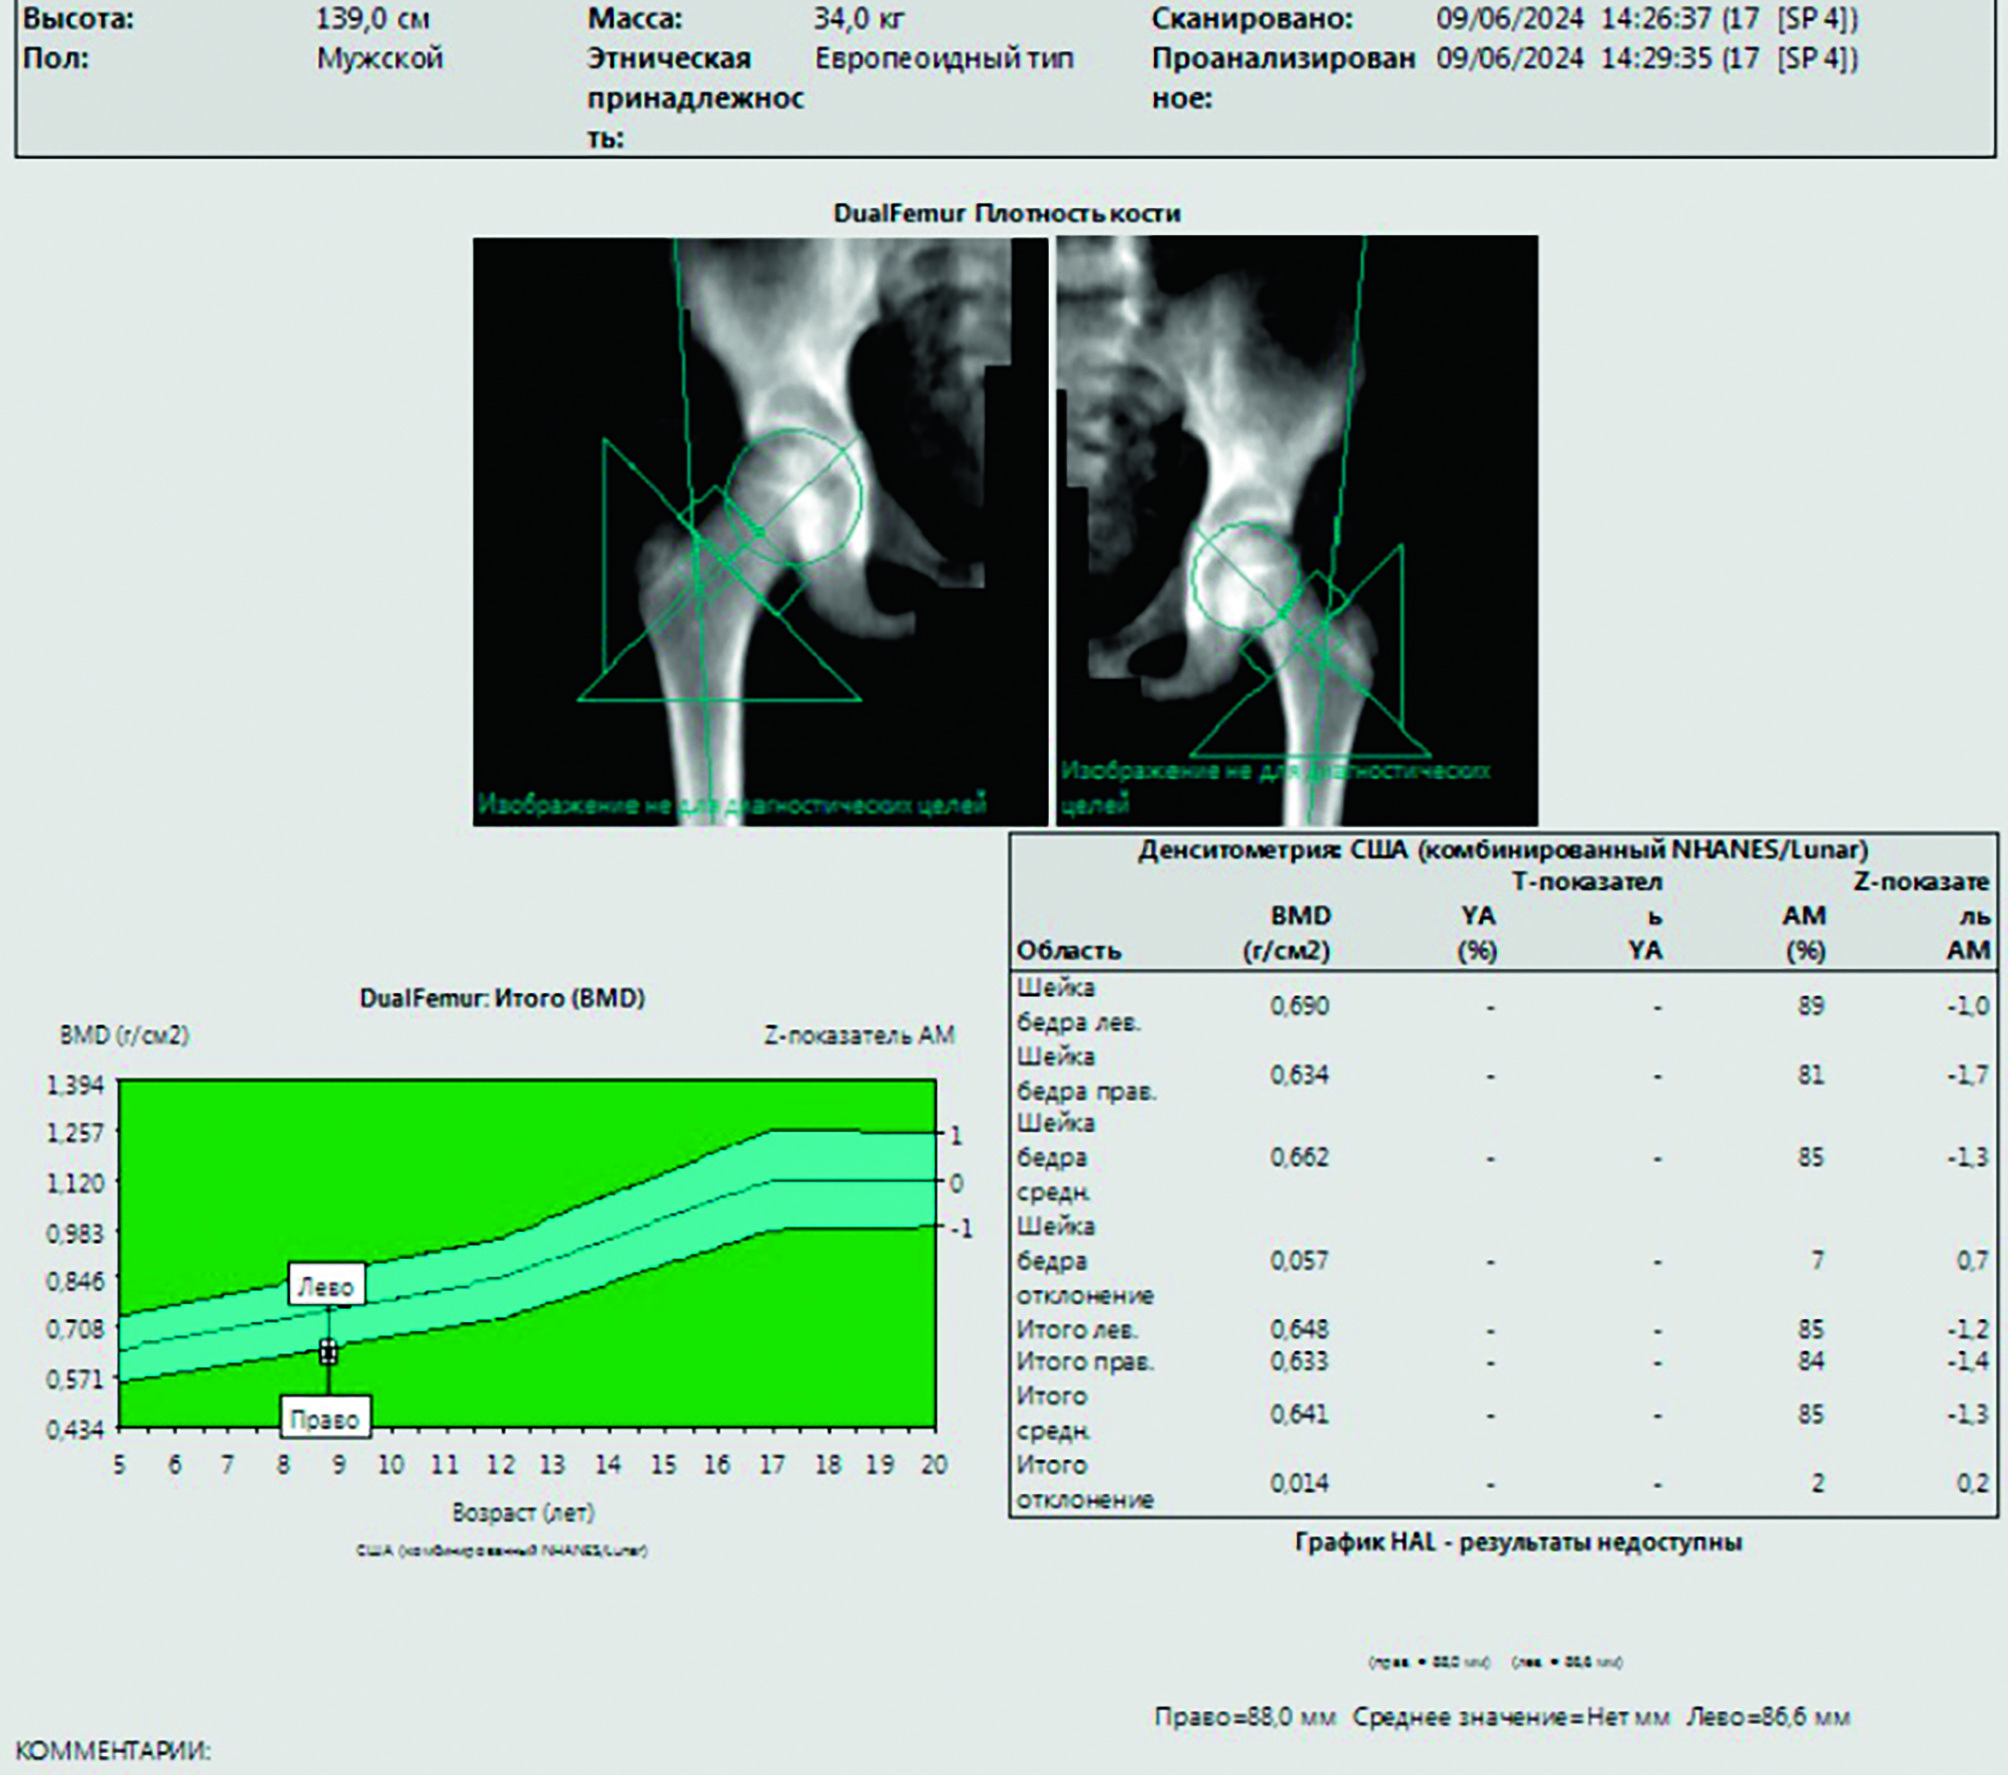

По данным проведенной остеоденситометрии бедренных костей от 17.07.2025: значения минеральной костной плотности в области шеек бедренных костей на уровне нижней границы нормы (рисунок 3).

Рисунок 3

Остеоденситометрия в области шеек бедренных костей: среднее значение BMD = 0,66 г/см2 находится в диапазоне нормальных значений (на уровне нижней границы нормы) минеральной плотности костной ткани относительно возраста

Figure 3

Densitometry in the area of the femoral necks: the mean BMD = 0.66 g/cm2 which is at the lower limit of the normal bone mineral density range for the patient’s age

Данные остеоденситометрии бедренных костей коррелируют с результатами МРТ-исследования, механизм смещения дифференцировки мезенхимальной стволовой клетки в сторону жировой ткани (адипоцитов) – один из доказанных патогенетических механизмов [21].